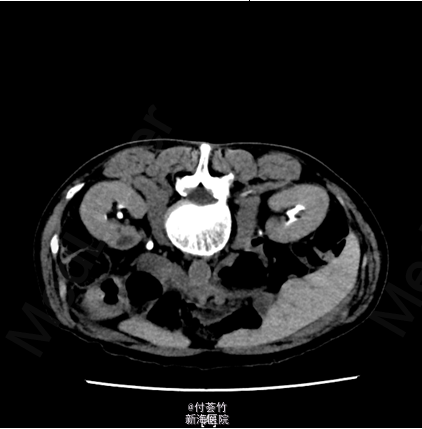

双肾区无红肿、隆起,无叩痛,双侧肋脊点、肋腰点无压痛。腹平软,双侧上中输尿管点无压痛,膀胱区无压痛。双侧腹股沟区未触及肿物 入院后查双肾CTU:膀胱结石,慢性膀胱炎,膀胱少许积气;左肾下部病灶,考虑良性病变,复杂囊肿可能大;双肾多发囊肿;前列腺电切术后改变,残留前列腺钙化